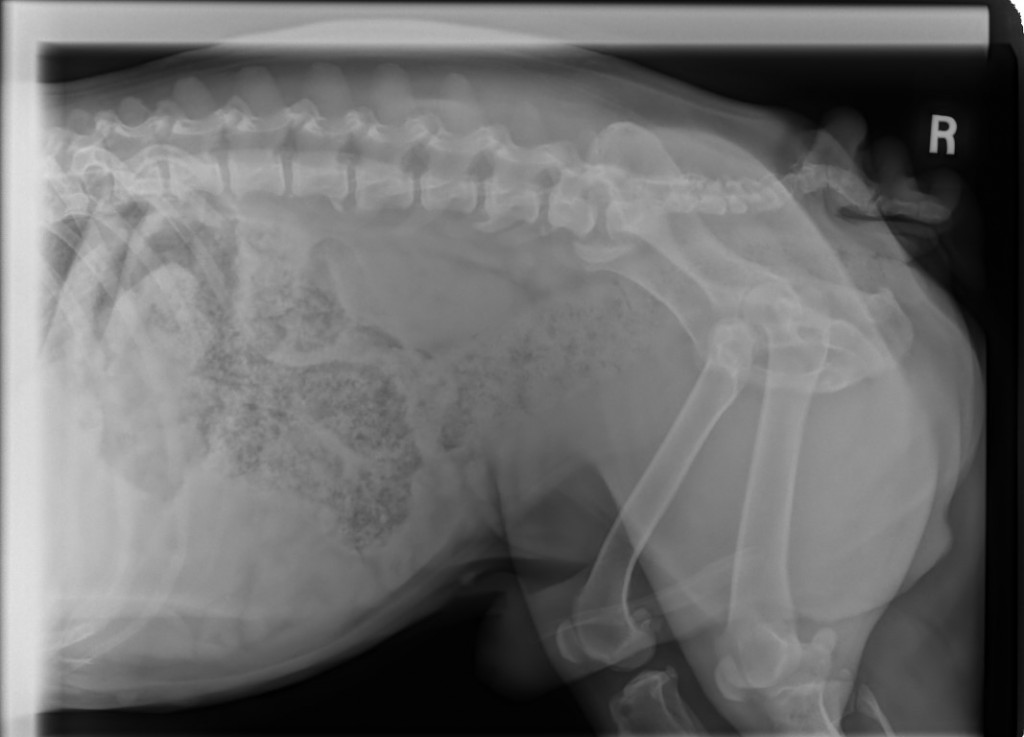

I took a look over his eyes and, they look fine. I looked at his chin and feet and, yes, they are definitely not great. I also looked at the one fold his temp foster wanted me to check and, it is slightly infected.

I told his temp foster mom that, my plan was to take him back for about 10 days, heal him up and, then bring him back. Should he react again, then we know for sure that the carpet, perhaps even laundry detergent, fabric softener, and, I did not even ask if they use anything like Febreeze, could well be the problem. We will know for sure then, that we do not want to see him in an approved adoptive home that has any carpets and, would have to be careful about other products used around him.

Even per his Vet at KAH, that he is on Baytril and, that he is battling these infections, is a bit concerning.

He has not had any incontinent issues since he was temp fostered as he is on the Baytril and that is wonderful news!!!